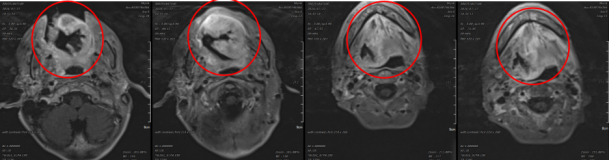

Figure 2: Pre-treatment MRI: A mass in the tongue and right tongue base (4.1x8.4cm) with abnormal enhancement, likely invasion of the adjacent soft palate, orbicularis oris muscle, and right epiglottis, with narrowing of the laryngopharyngeal cavity at the same level.